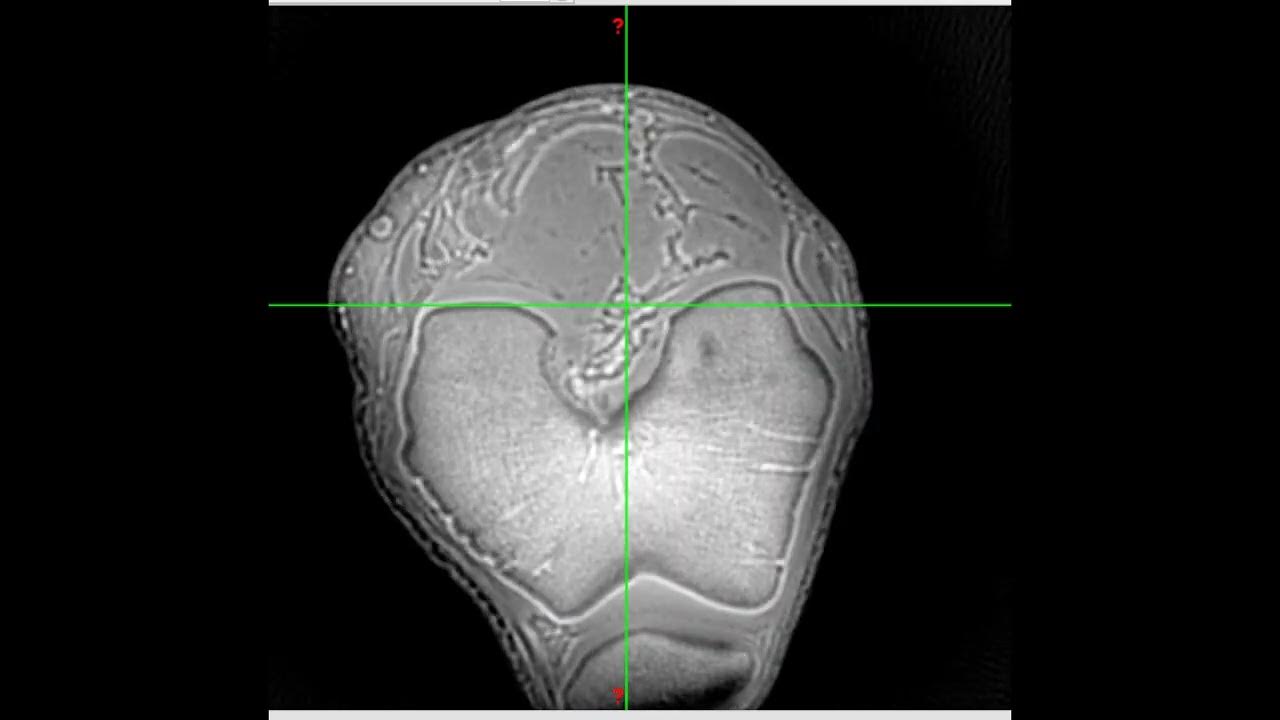

A coronal ultrashort echo time sequence in a 10yearold boy with Short Echo Time It determines when the signal is measured during the relaxation process. The echo time (te) refers to the time between the application of the radiofrequency excitation pulse and the peak of. Tr and te are basic pulse sequence parameters and stand for repetition time and echo time respectively. Echo time (te) definition of te: This review paper summarizes recent technical. Short Echo Time.

—MR ultrashort echo time (UTE) acquisitions for showing the cortical Short Echo Time Te is the time between the application of the rf pulse and the peak of the signal (echo) detected in the receiver coil. They are typically measured in. Echo time (te) definition of te: This review article summarizes recent technical developments in ultrashort echo time (ute) magnetic resonance imaging of. Tr and te are basic pulse sequence parameters and stand. Short Echo Time.